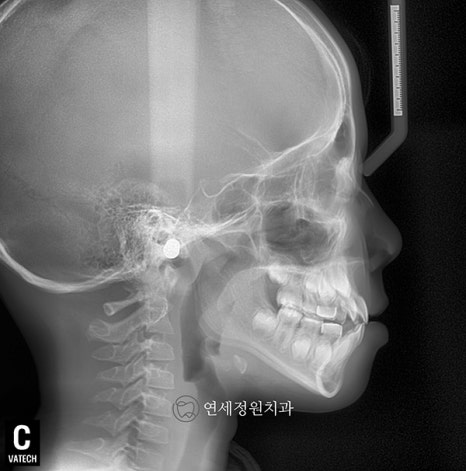

얼마 전 반가운 환자가 연세정원치과에 내원해주었습니다. 이 환자와의 인연은 9년 전 2015년 10월에 시작되었습니다. 만 7세 여자아이로 앞니가 반대로 물리는 반대교합을 주소로 처음 내원한 환자였습니다.

전치부 반대교합은 발견되는 즉시 개선해주는 것이 가장 좋습니다. 앞니가 반대로 물리는 반대교합의 개선을 위하여 페이스마스크 치료를 시작하였습니다. 보호자분과 환자의 협조도가 좋아 짧은 기간 내에 전치부 반대교합이 개선되었습니다. 반대교합이 개선된 이후 FRIII (프랑켈 장치) 로 유지를 해주었습니다.

2016년 10월